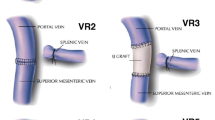

Considering that two anastomoses are required, in type 4 vein resection and reconstruction initially only the SMV is crossclamped to maintain some portal flow through the splenic vein. Actually, if the inferior mesenteric vein drains into the splenic vein, also some venous outflow from the intestine may be maintained (Fig. 9). Once everything is ready for reconstruction the interposition graft is inserted into the abdomen. A suture is placed at the distal margin of conduit to facilitate graft orientation and handling. The anastomosis between the SMV and the interposition graft is performed first, using two half-running sutures as described for type 3 vein reconstruction. Next, splenic and portal veins are crossclamped, the SMV is divided near the spleno-mesenteric junction, the graft is trimmed at the appropriate length, and the second anastomosis is fashioned using the same technique described above (Fig. 10) (video 4).

Type 4 vein resection and reconstruction. When resection involves the proximal portion of the superior mesenteric vein, portal flow can be maintained through the splenic vein (arrows). From Boggi U (Ed.) Minimally Invasive Surgery of the Pancreas. Springer-Verlag Italia s.r.l. 2018 – https://doi.org/10.1007/978-88-470-3958-2